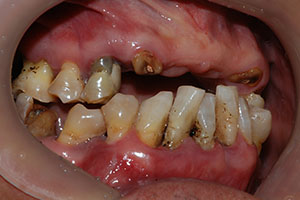

치료증례 전후사진

Before & After